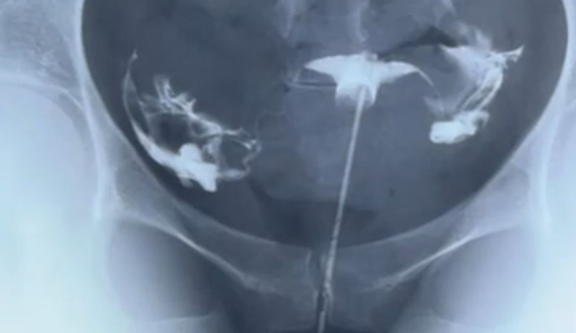

Для выполнения процедуры пациенте нужно лечь в гинекологическое кресло. Врач наносит местный анестетик на слизистую шейки матки, после чего через гибкий катетер вводит в полость матки небольшой объем физиологического раствора. Затем доктор оценивает распределение жидкости с помощью ультразвукового аппарата. В норме раствор попадает в обе маточные трубы и проникает в брюшную полость.